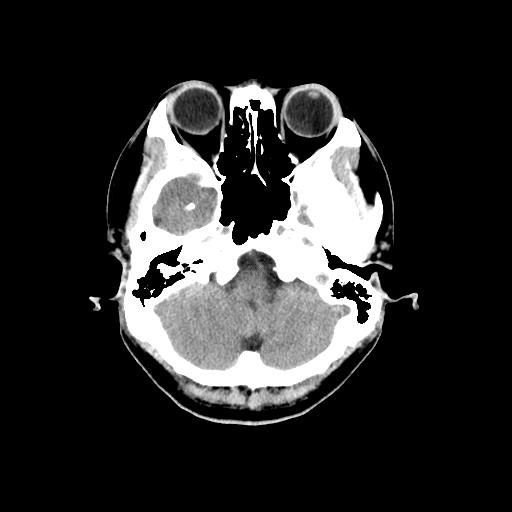

CT検査は様々な方向からX線を当て体内の水分や骨、空気など成分の違いを区別して画像を生成することで、レントゲン等では得ることができない臓器の状態を詳細に把握することが可能となり、小さい腫瘍などをより明確に映し出すことができます。

また、多角的に体内の断面図を得ることができるため立体的に構造を理解することが可能になり、病変の位置や広がりをより詳細に判断することが可能になります。

CT装置は列数が多くなると一度に広範囲の撮影が可能となり、息止め時間が短くなるため少ない負担で検査を受けて頂けます。また、より細かい断層(輪切り)画像を撮る事ができ、病変の抽出能が上がることは早期発見に繋がります。